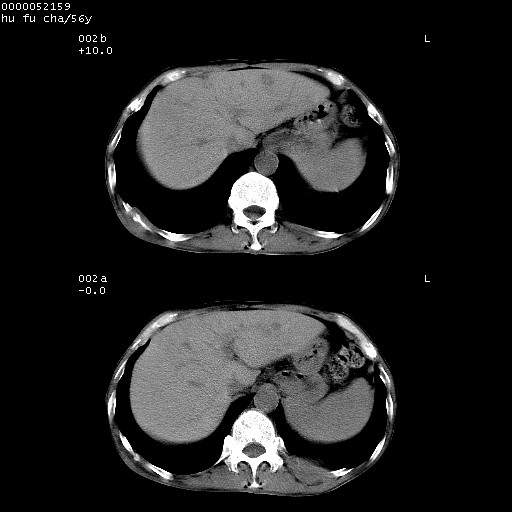

以下是引用zsl6918在2008-8-25 22:47:00的发言:[br]胸骨,胸椎及肋骨均可见多发转移表现,肝内低密度结节不除外转移。原发灶可能在右肺。双侧可见支扩表现。

以下是引用宇宙ct在2008-8-25 23:26:00的发言:[br][br] 胸骨,胸椎及肋骨均可见多发转移表现,肝内低密度结节不除外转移。原发灶可能在右肺。双侧可见支扩表现。 [br] [br]

以下是引用卜一在2008-8-26 8:02:00的发言:[br][br] 支持:肺癌并肺内,胸骨,胁骨,胸椎及肝内转移!另:左肺支气管扩张征伴感染! [br]

以下是引用zjzjr在2008-8-26 11:03:00的发言:[br]支持:肺癌并肺内,胸骨,胁骨,胸椎及肝内转移!另:左肺支气管扩张征伴感染!